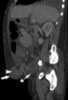

Incarcerated hernia

A hernia is the abnormal exit of tissue or an organ, such as the bowel, through the wall of the cavity in which it normally resides. Hernias come in a number of types. [Source: Wikipedia ]